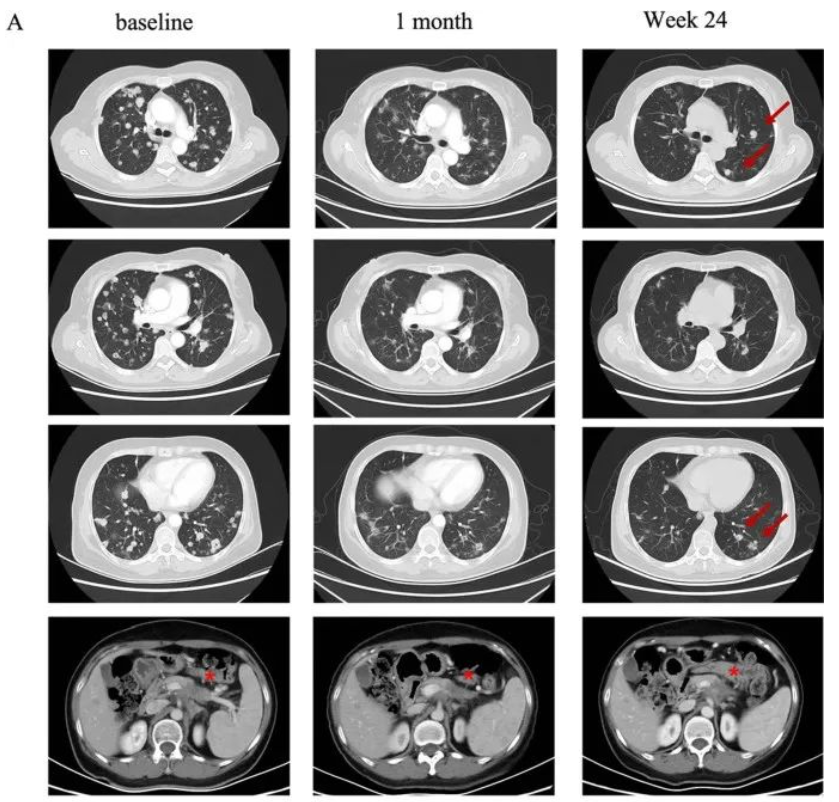

58岁女性胰腺癌患者,多种方案无效,肿瘤持续进展。2021年入组了CAR-T疗法的临床实验。2021年9月,接受了250×10^6剂量的CT041细胞回输,靶病灶显著缩小30%以上,评效达到部分缓解(PR),肺转移也出现了大幅缩小!

75岁女性胰腺癌手术后仅5个月就出现了肺部转移,接受化疗方案无效,病情迅速进展。250 × 10^6剂量的CT041细胞回输后仅4周后的复查竟显示肿瘤显著缩小,而肺转移靶病灶随后消失并且评效达到完全缓解(CR)! 直到2023年7月最后一次随访时,肿瘤仍得到良好控制。